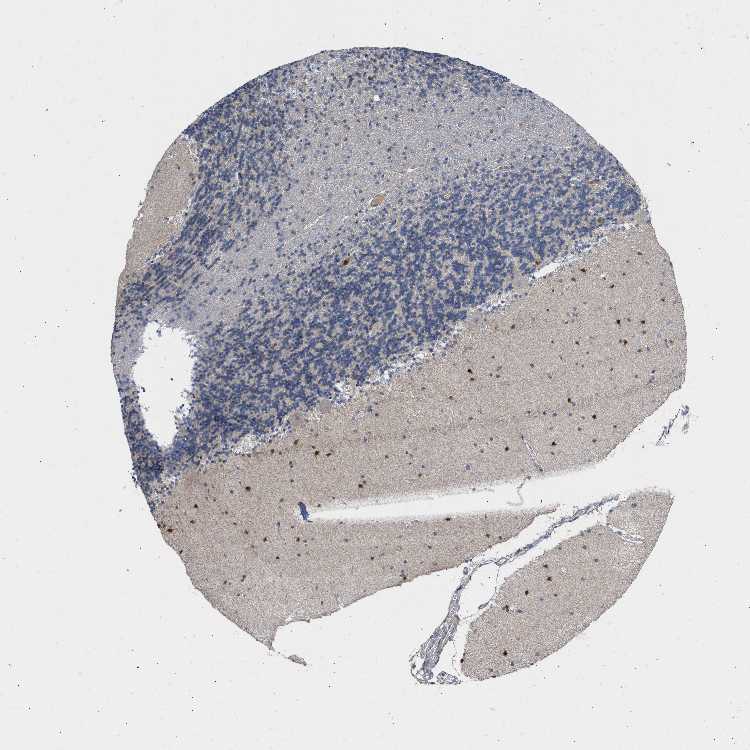

CEREBELLUM - Antibody stainingi

Antibody staining in the annotated cell types in the current human tissue is reported as not detected, low, medium, or high, based on conventional immunohistochemistry profiling in selected tissues. This score is based on the combination of the staining intensity and fraction of stained cells.

Each image is clickable and will lead to virtual microscopy that enables deeper exploration of all samples and also displays staining intensity scores, fraction scores and subcellular localization as well as patient and tissue information for each sample.

Antibody HPA020725

Purkinje cells Not detected

Cells in granular layer Not detected

Cells in molecular layer Medium